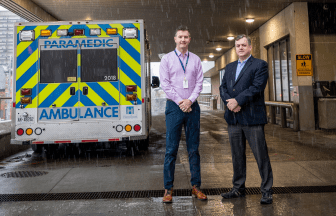

St. Joe’s seeks to add CT scanner to its emergency department to reduce wait times, code zerosSt. Joseph's Healthcare is asking for help meeting its goal of bringing a CT scanner into the emergency department to reduce wait times and cut down on ambulance offloading delays.HealthDec 3, 2021

![]()